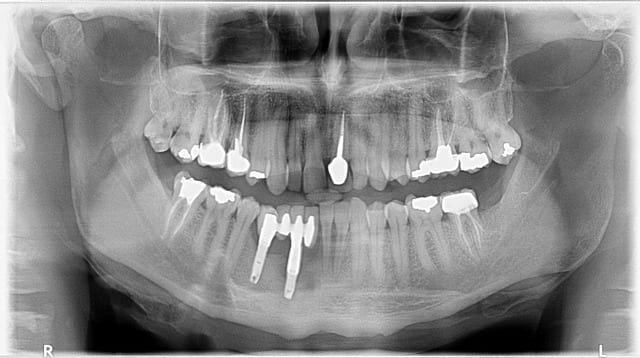

Pour le plaisir de participer...

Technique brésilienne.

mais ca tient depuis quand ce truc, c'est dingue ca quand même

En fait le truc tient depuis 20 ans !

Tenu 30 ans à la brésilienne aussi

ca serait-y pas des implants en tantale?

Ohhh les jolis implants aiguilles, des lustres que j'en avais pas vu... ça fait partie de l'histoire !